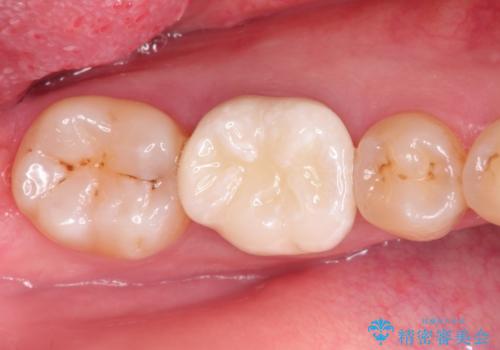

奥歯が痛い。根管治療~オールセラミッククラウン

- 奥歯の痛みを主訴に来院されました。

検査の結果、神経は保存不可能と診断されたため、根管治療~オールセラミッククラウンによる治療を行いました。